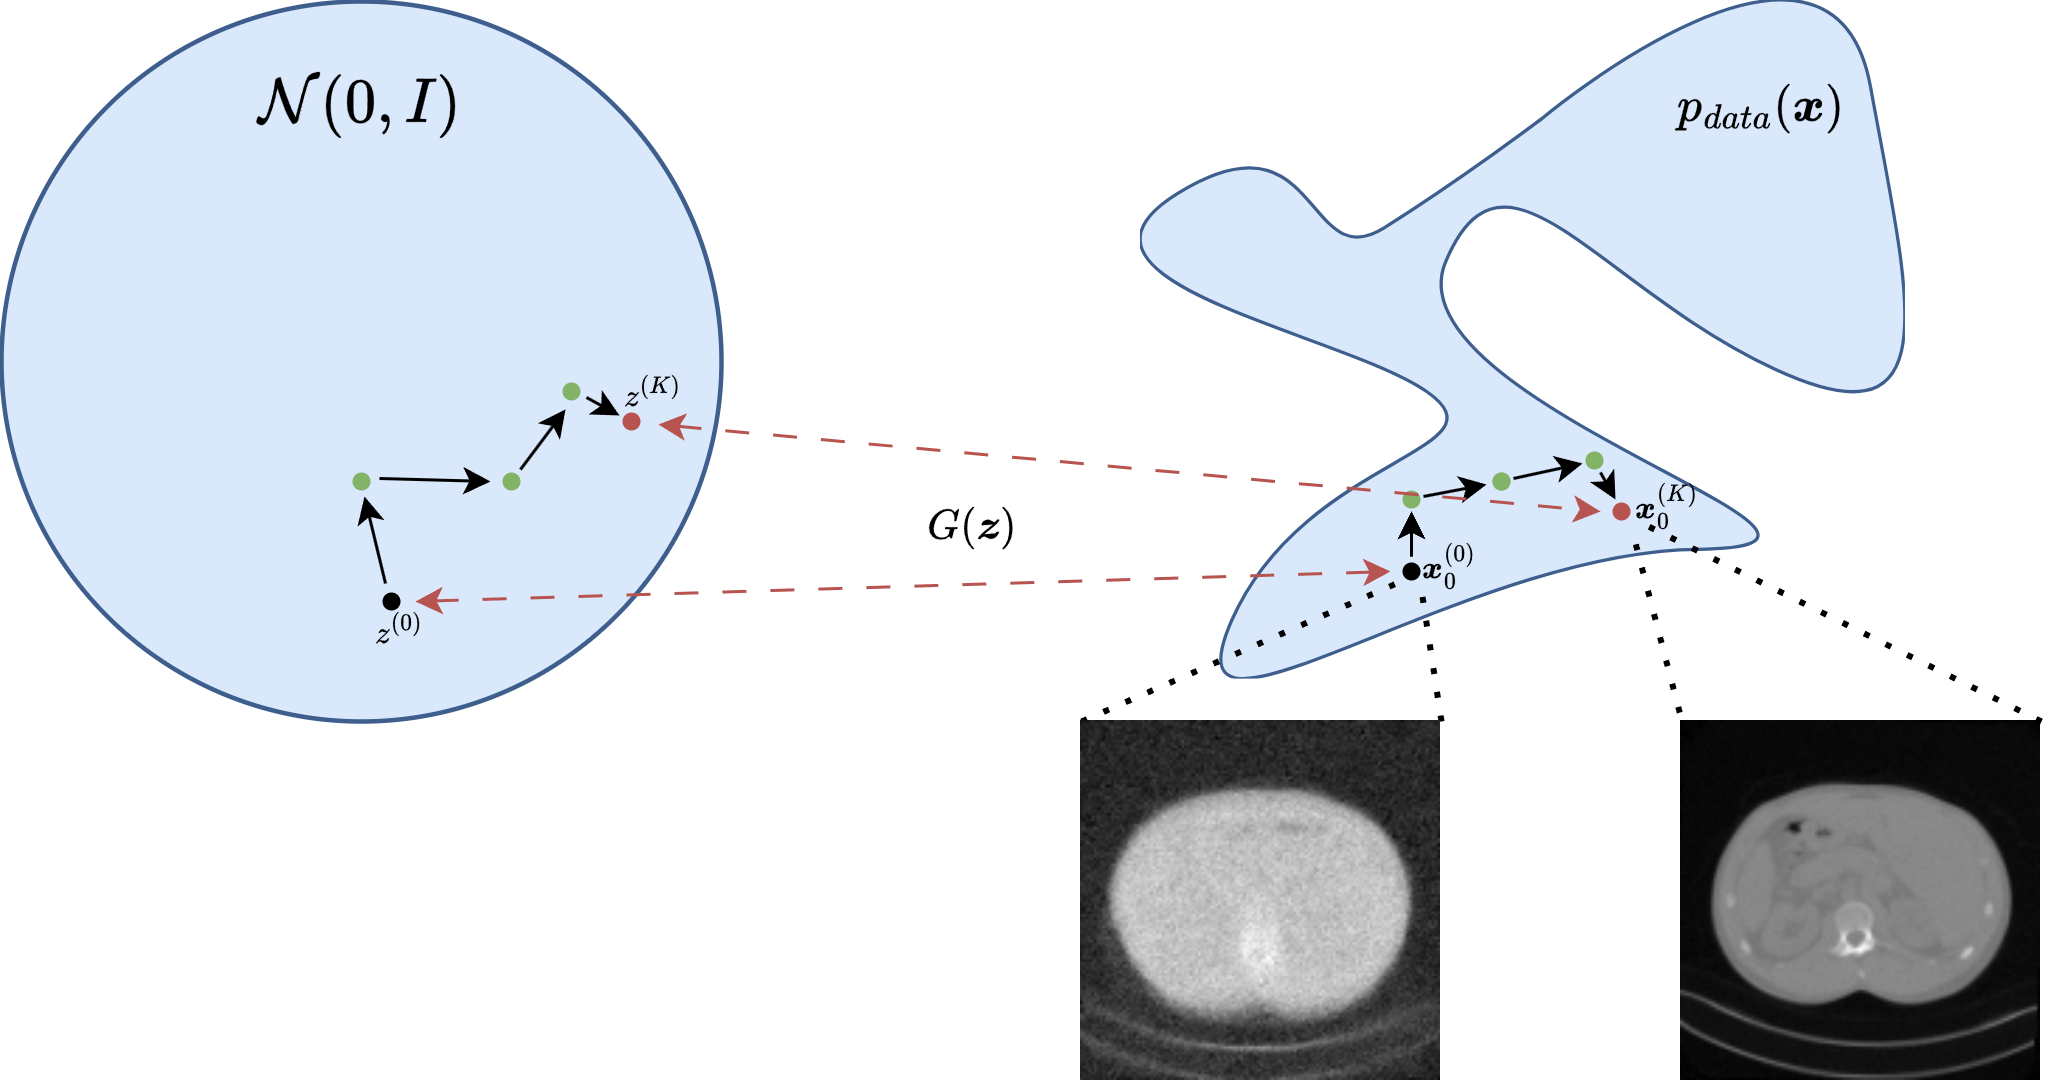

One of the first influential ways to connect deep generative models with inverse problems is the Deep Generative Prior (DGP) viewpoint [6, 14, 30, 35]. The central idea is to replace a hand-crafted prior, such as sparsity or total variation, with a pretrained generator \(G\). The prior is therefore enforced not by a penalty written directly on the image, but by restricting the reconstruction to the family of images that the network can generate.

If the unknown image is assumed to lie approximately in the range of a generator \(G\), then one can search for a latent code whose generated image explains the data:

\[ \widehat{\boldsymbol{z}} = \operatorname*{arg\,min}_{\boldsymbol{z}} \; \|K G(\boldsymbol{z}) - \boldsymbol{y}^\delta\|_2^2 + \lambda \|\boldsymbol{z}\|_2^2. \]

The reconstruction is then

\[ \widehat{\boldsymbol{x}} = G(\widehat{\boldsymbol{z}}). \]

This gives a useful geometric interpretation. The generator defines a nonlinear low-dimensional set

\[ \mathcal{M} = \{ G(\boldsymbol{z}) : \boldsymbol{z} \in \mathbb{R}^d \} \subset \mathbb{R}^n, \]

and the inverse problem is solved over \(\mathcal{M}\) instead of the whole ambient image space. When \(d \ll n\), the search space is dramatically reduced, and the reconstruction automatically inherits anatomical, textural, and structural regularities learned from training data.

From a Bayesian viewpoint, this is a latent-variable MAP estimator. One starts from a simple latent law, often \(\boldsymbol{z} \sim \mathcal{N}(\boldsymbol{0}, I)\), pushes it through the generator, and thereby induces a prior on images. In the VAE case, the decoder plays the role of \(G\) and the latent prior is built into the model. In the GAN case, the generator is explicit, but the induced image density is usually implicit rather than analytically tractable.

../_images/DGP.png

A useful practical detail is that one may optimize only \(\boldsymbol{z}\), or augment the model with a small correction term to reduce range mismatch. The pure DGP formulation is the cleanest conceptually, but it is also the one most exposed to representation error: if the true image cannot be written well as \(G(\boldsymbol{z})\), then even perfect optimization cannot recover it exactly.